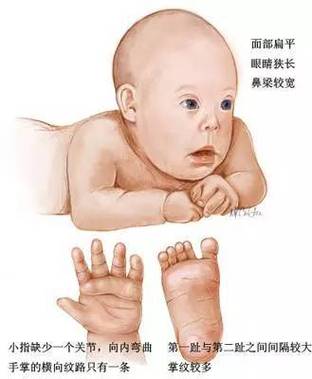

唐氏综合征(又称21三体综合征)是一种由第21号染色体多出一条而引起的染色体异常疾病,孕期筛查和诊断的目的是评估胎儿患有唐氏综合征的风险。

- 鼻骨缺失或发育不良:在孕11-13+6周的B超中,如果发现胎儿鼻骨未显示或过短,是唐氏综合征的一个重要软指标。

- 长骨股骨/肱骨短小:胎儿的腿或手臂长骨测量值低于相应孕周的正常范围。

- 心脏结构异常:部分唐氏综合征患儿会伴有先天性心脏病,如室间隔缺损、房间隔缺损等,需要系统胎儿超声心动图检查才能发现。